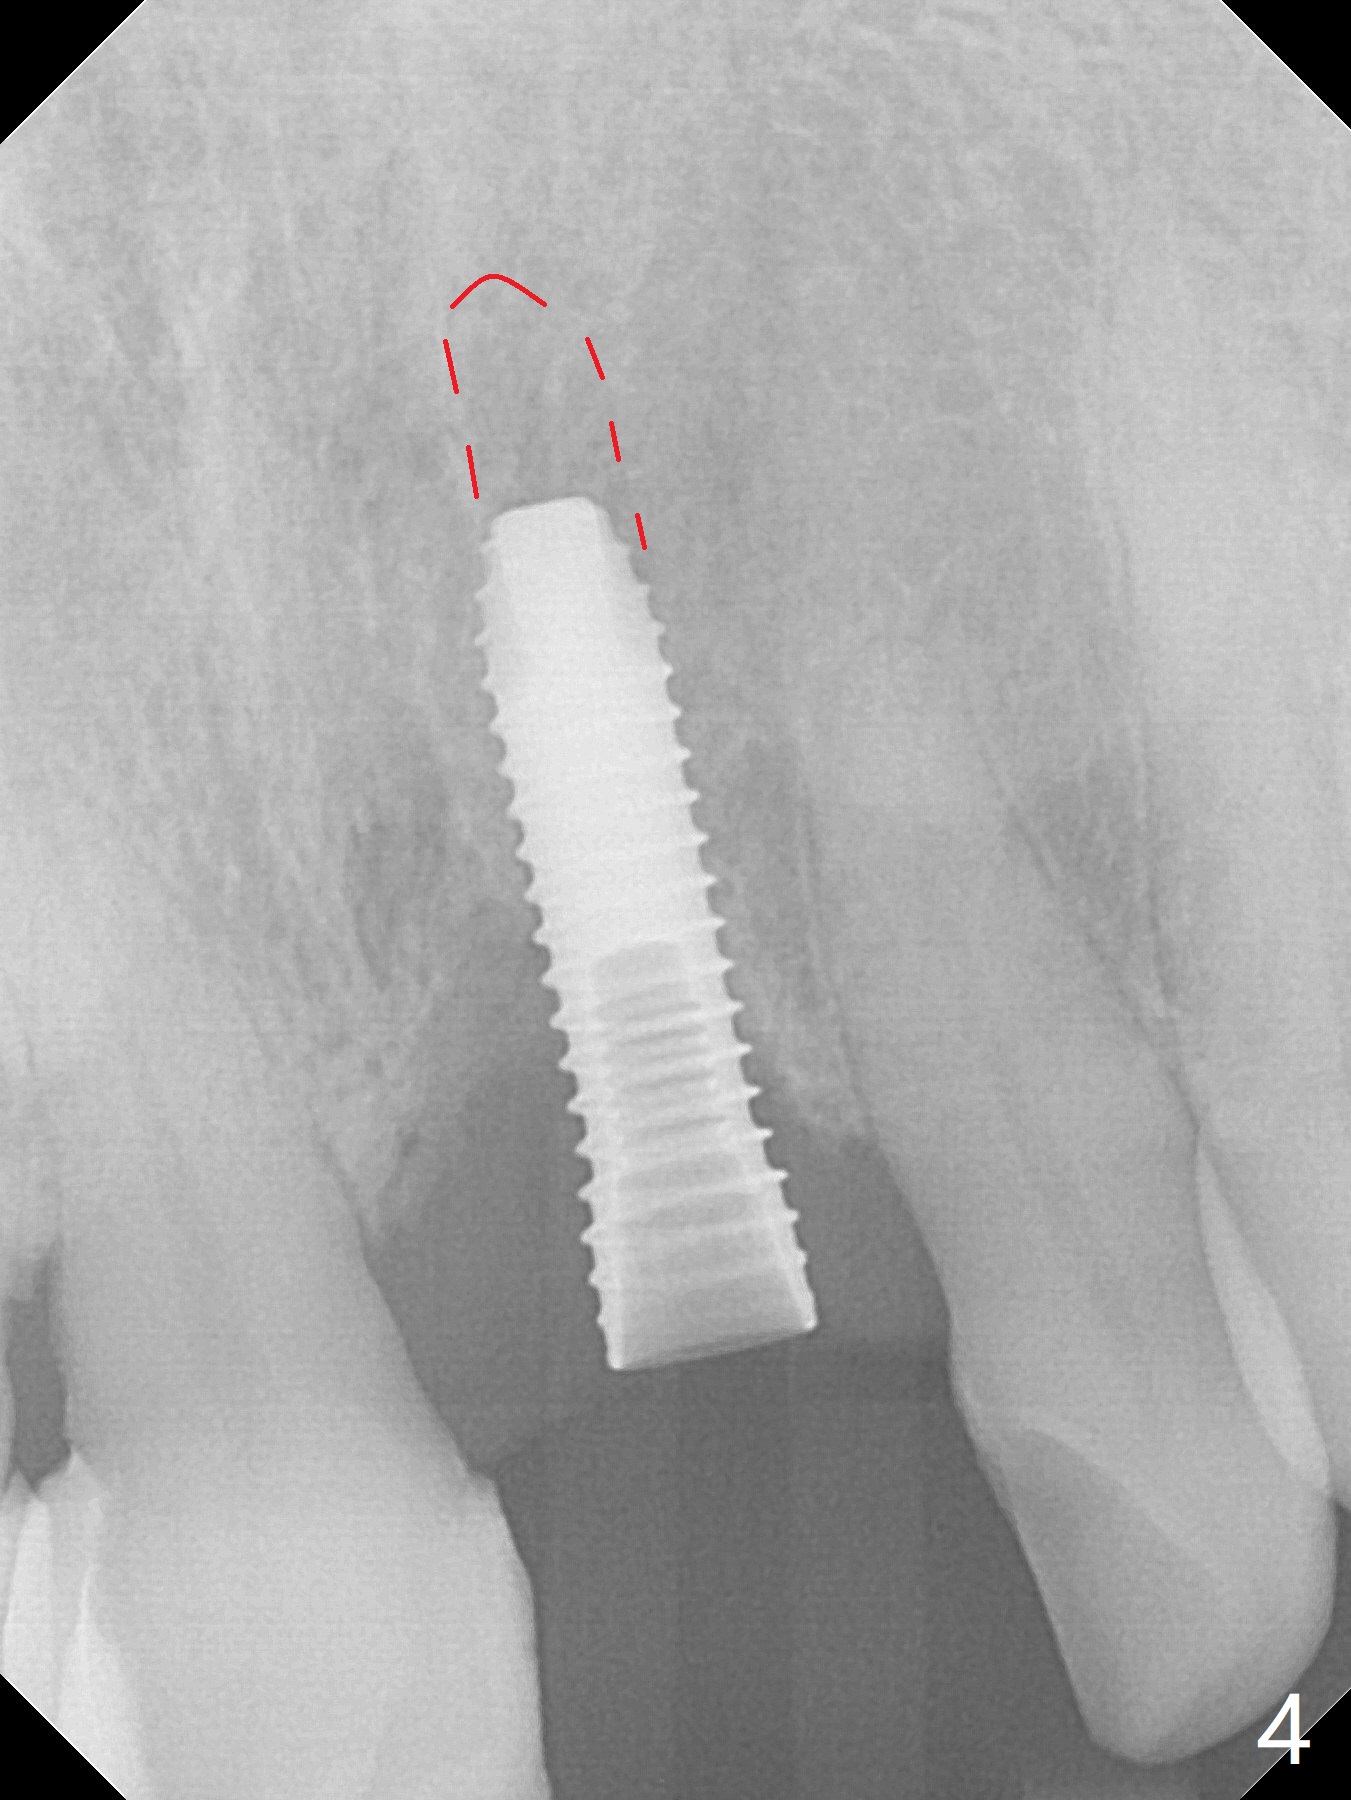

In spite of the incisobuccal shift of the tooth #9 with gingival recession (Fig.1) and loss of the buccal plate (intraop finding), there is no buccal contour collapse (Fig.2 *), due to the presence of the buccal bone of the neighboring teeth and the root of the affected tooth. After extraction, osteotomy (Fig.3) and dummy implant try in (Fig.4), a definitive implant is placed palatally with the buccal gap (Fig.5 *). In fact there is mild buccal contour collapse prior to bone graft (Fig.5 arrow). When allograft (Vera, Fig.6,7 *) is packed buccal to the implant and overlying abutment as a solid support, the buccal contour seemingly returns normal (Fig.6 arrowhead). An immediate provisional is fabricated to prevent loss of the bone graft during healing period. Bone graft kept in place by the provisional turns yellow 6 days postop (Fig.8). The buccal plate remains strong, while the fistula becomes indistinguishable. After adjustment of the provisional margin a few times (nearly 3 months postop, Fig.9,10), the gingival margin appears to have grown incisally, as compared to Fig.1. There is minimal buccal bone collapse (Fig.10). Dislodgement of the abutment and provisional forces her to return 1 year 4 months postop; the socket has healed (Fig.11). The buccal plate is not concave 1 year 4 months postop (Fig.12). The gingiva is slightly recessive (Fig.13) with mild buccal plate concavity (Fig.14) immediately before cementation. The implant could be placed ~ 1 mm deeper (Fig.15).